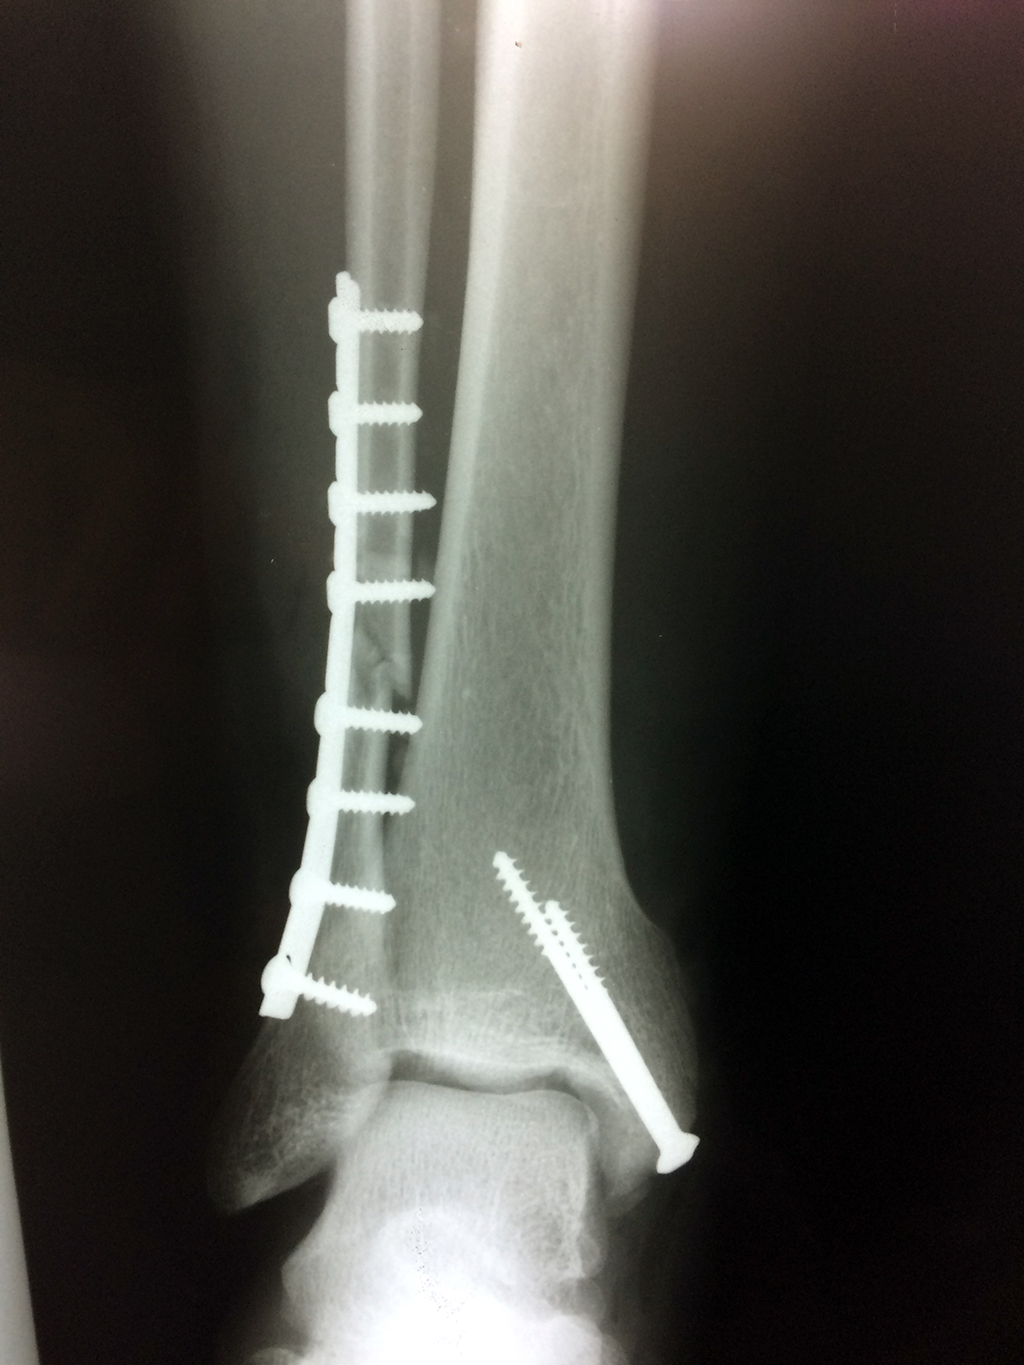

Cuando se necesita cirugía, es probable que esta implique el uso de clavijas de metal, tornillos o placas para sostener los huesos en su lugar mientras la fractura se consolida. Los elementos de soporte pueden ser temporales o permanentes.

Algunas fracturas de tobillo pueden requerir cirugía si:

- Los extremos de los huesos están desalineados entre sí (desplazados).

- La fractura se extiende hasta la articulación del tobillo (fractura intra-articular).